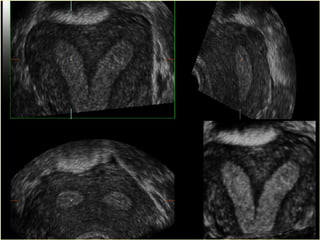

Congenital Uterine Anomaly n Precise incidence is unknown (range from 1-2 %) n  Clinical presentation: 1 Usually asymptomatic 2 Menstrual disorder 3 Dysmenorrhea 4 Recurrent abortion ( decrease intrauterine volume and vascularity, increase uterine irritability and cervical incompetance ) 5 Premature labor 6 Abnormal presentation 7 Primary infertility

Congenital Uterine Anomaly n Diagnosis: History Pelvic exam Hysterosalpingography U/S MRI Laproscopy Hysteroscopy IVP or U/S (Exclude Renal anomaly )

Congenital Uterine Anomaly n Treatment: 1- Double uterus (didelphic uterus): no need to treat. 2- Bicornate ut. --------- Strassmann procedure ( if indicated ) 3- Ut. Septum --------- (BCP for dysmenorrhea ), Tompkins metroplasty or Hysteroscopic resection of septum ) 4- Unicornate ut. -------- Surgery indicated if there is blind horn which cause symptom----- surgical resection of blind horn.